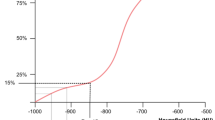

Our data yields a sparseness indicator of ψ < 0.1 for the attenuation data of both groups H and C (see Eq. 1 quantifying sparseness for vector v[1,…,n] with ψ = 0 for dense and ψ = 1 for maximally sparse vectors which uses an l1/l2-norm penalization [20] ). However, this indicates that Wald statistics are applicable in this instance [21] as no Hauck-Donner effect should be expected. Subsequently, a General Linear Model (GLM) [22] assuming a binomial data distribution to determine membership to either H or C (equal group sizes) was employed in order to perform and plot [23] a logistic regression (Fig. 5).

Logistic regression derived from a General Linear Model shows that given our data (and its inclusion and exclusion criteria), a 90 % probability for fatal hypothermia exists for PMCT lung attenuation of less than −780 HU, whereas based on this data, the probability for missing fatal hypothermia is less than 10 % for PMCT lung attenuation exceeding −590 HU. Test data (triangle pointing down hypothermia, triangle pointing up not hypothermia) was fitted to test the model, details see Table 2

Determination of probability for group T members to be either hypothermic or not hypothermic was achieved by inserting lung PMCT attenuation data of T into the fitted GLM.

Predicting fatal hypothermia

Fatal hypothermia may be suspected based on the criteria listed above and PMCT findings in a new case. To test that assumption, ten test cases (group T) were evaluated using the GLM (i.e., the statistical model) that had been determined based on existing data of groups H and C.

The logistic regression curve (see Fig. 5) derived from the GLM shows a significant statistical effect of pulmonary PMCT attenuation on group membership H or C (given their group definitions), respectively (Wald statistic: p < 0. 001). The GLM also predicted that given our test data (and its inclusion and exclusion criteria), there would be a 90 % probability for hypothermia with PMCT lung attenuation of less than −780 HU, whereas the probability for overlooking hypothermia is less than 10 % for PMCT lung attenuation greater than −590 HU.

The seven hypothermic cases of test group T were successfully predicted to be hypothermic based on PMCT lung density alone, with a probability of 94 %. The three control cases of group T yielded an average fatal hypothermia probability of 21 %.

To illustrate the test results given by the model, test case CT densities were plotted alongside the fitted model data as triangles (see Fig. 5).

Lung attenuation of less than −780 HU appeared to correlate with an observed probability of hypothermic death exceeding 90 % (excluding drowning, gaseous, and mechanical asphyxia such as strangulation and carbon monoxide poisoning). A predictive probability derived from Generalized Linear Model that we determined from study groups H and C placed a 94 % probability on seven new test cases of fatal hypothermia compared to a 21 % probability for three non hypothermic deaths in the test group. The question is, what does this observation mean?